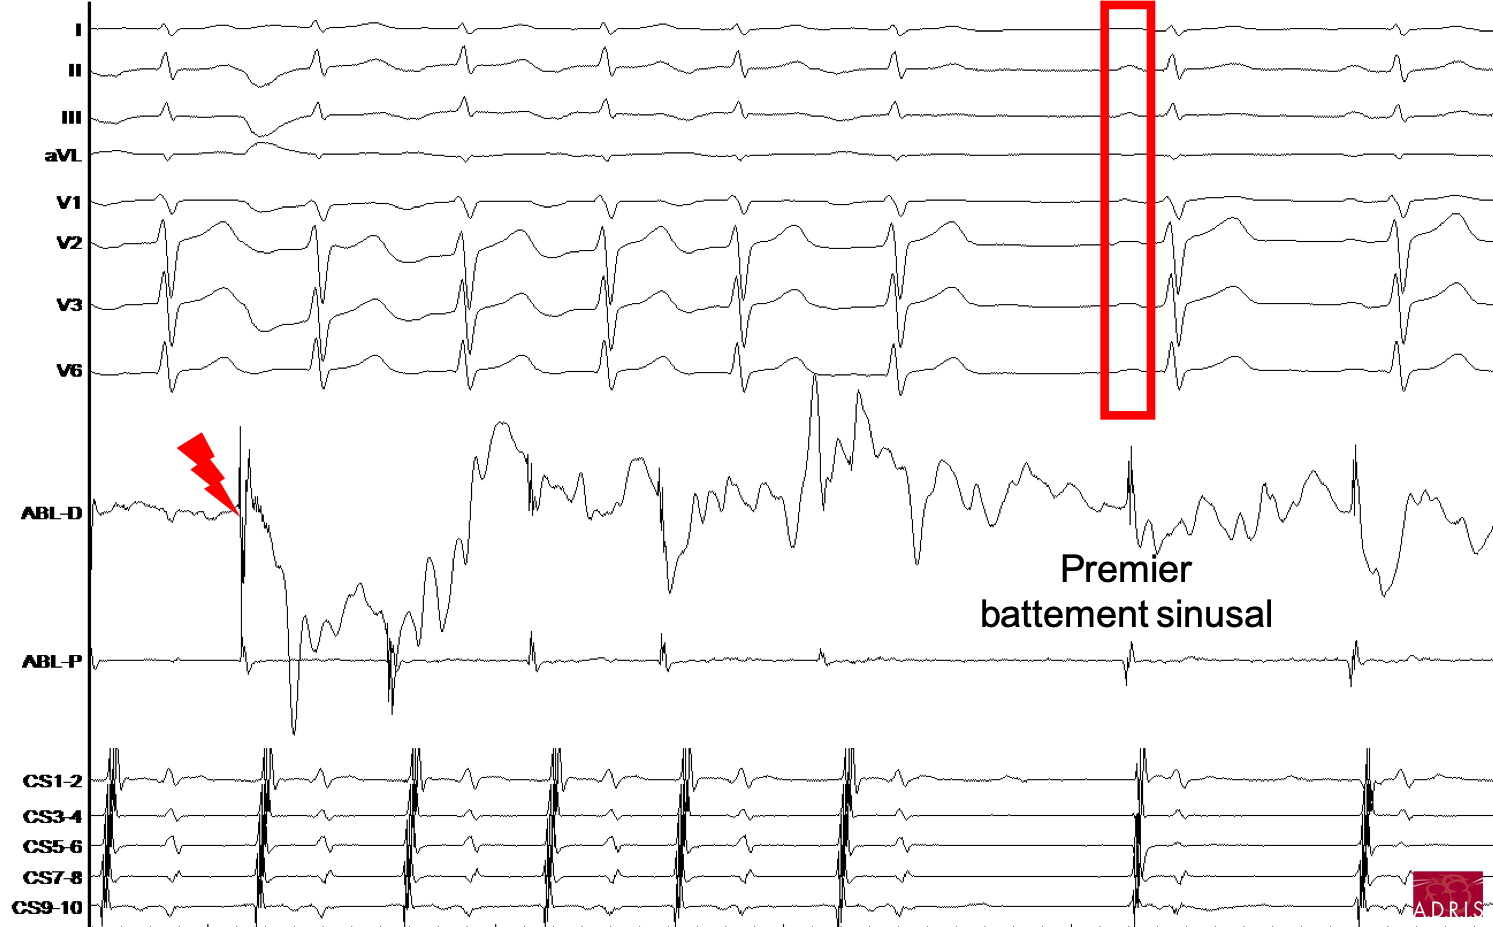

Ablation de tachycardie atriale focale droite, paroi inférolatéral, proche de l'anneau tricuspide chez un patient de 23 ans.